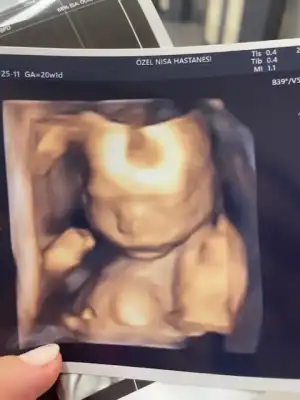

idrar yolu enf olmamışım yanlış görmüş aile hekimim 😜😜gitmişken bi baktı doktor 400 gram 25 cm olmuş hanımefendi keyfimiz yerinde 🥰

• A690F5EE-80BB-4182-B7D5-56E28E2D0FB4.webp

A690F5EE-80BB-4182-B7D5-56E28E2D0FB4.webp

12,4 KB · Görüntüleme: 84